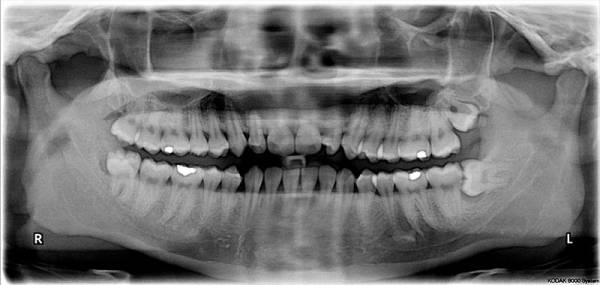

Gli elementi dentali cominciano a formarsi dai 10 12 anni ed in ortopanoramiche eseguite in quell´età già si possono evidenziare le gemme dentali in via di formazione. Le gemme crescono nel contesto dell´osso ma data la loro localizzazione nella porzione più posteriore delle arcate dentali e formandosi con pochissimo spazio a disposizione possono orientarsi in maniera erronea avendo successivamente limitata o completamente abolita la possibilità di emergere in arcata.

La crescita dei denti del giudizio dovrebbe essere monitorata attraverso una RX ortopanoramica a cominciare dai 16-17 anni. Se si evidenziano anomalie di crescita conviente estrarre tali elementi prima che le radici completano la loro formazione. Generalmente conviene togliere i dneti del giudizio che non riescono ad emergere per via della loro inclinazione tra i 16 ed i 20 anni.